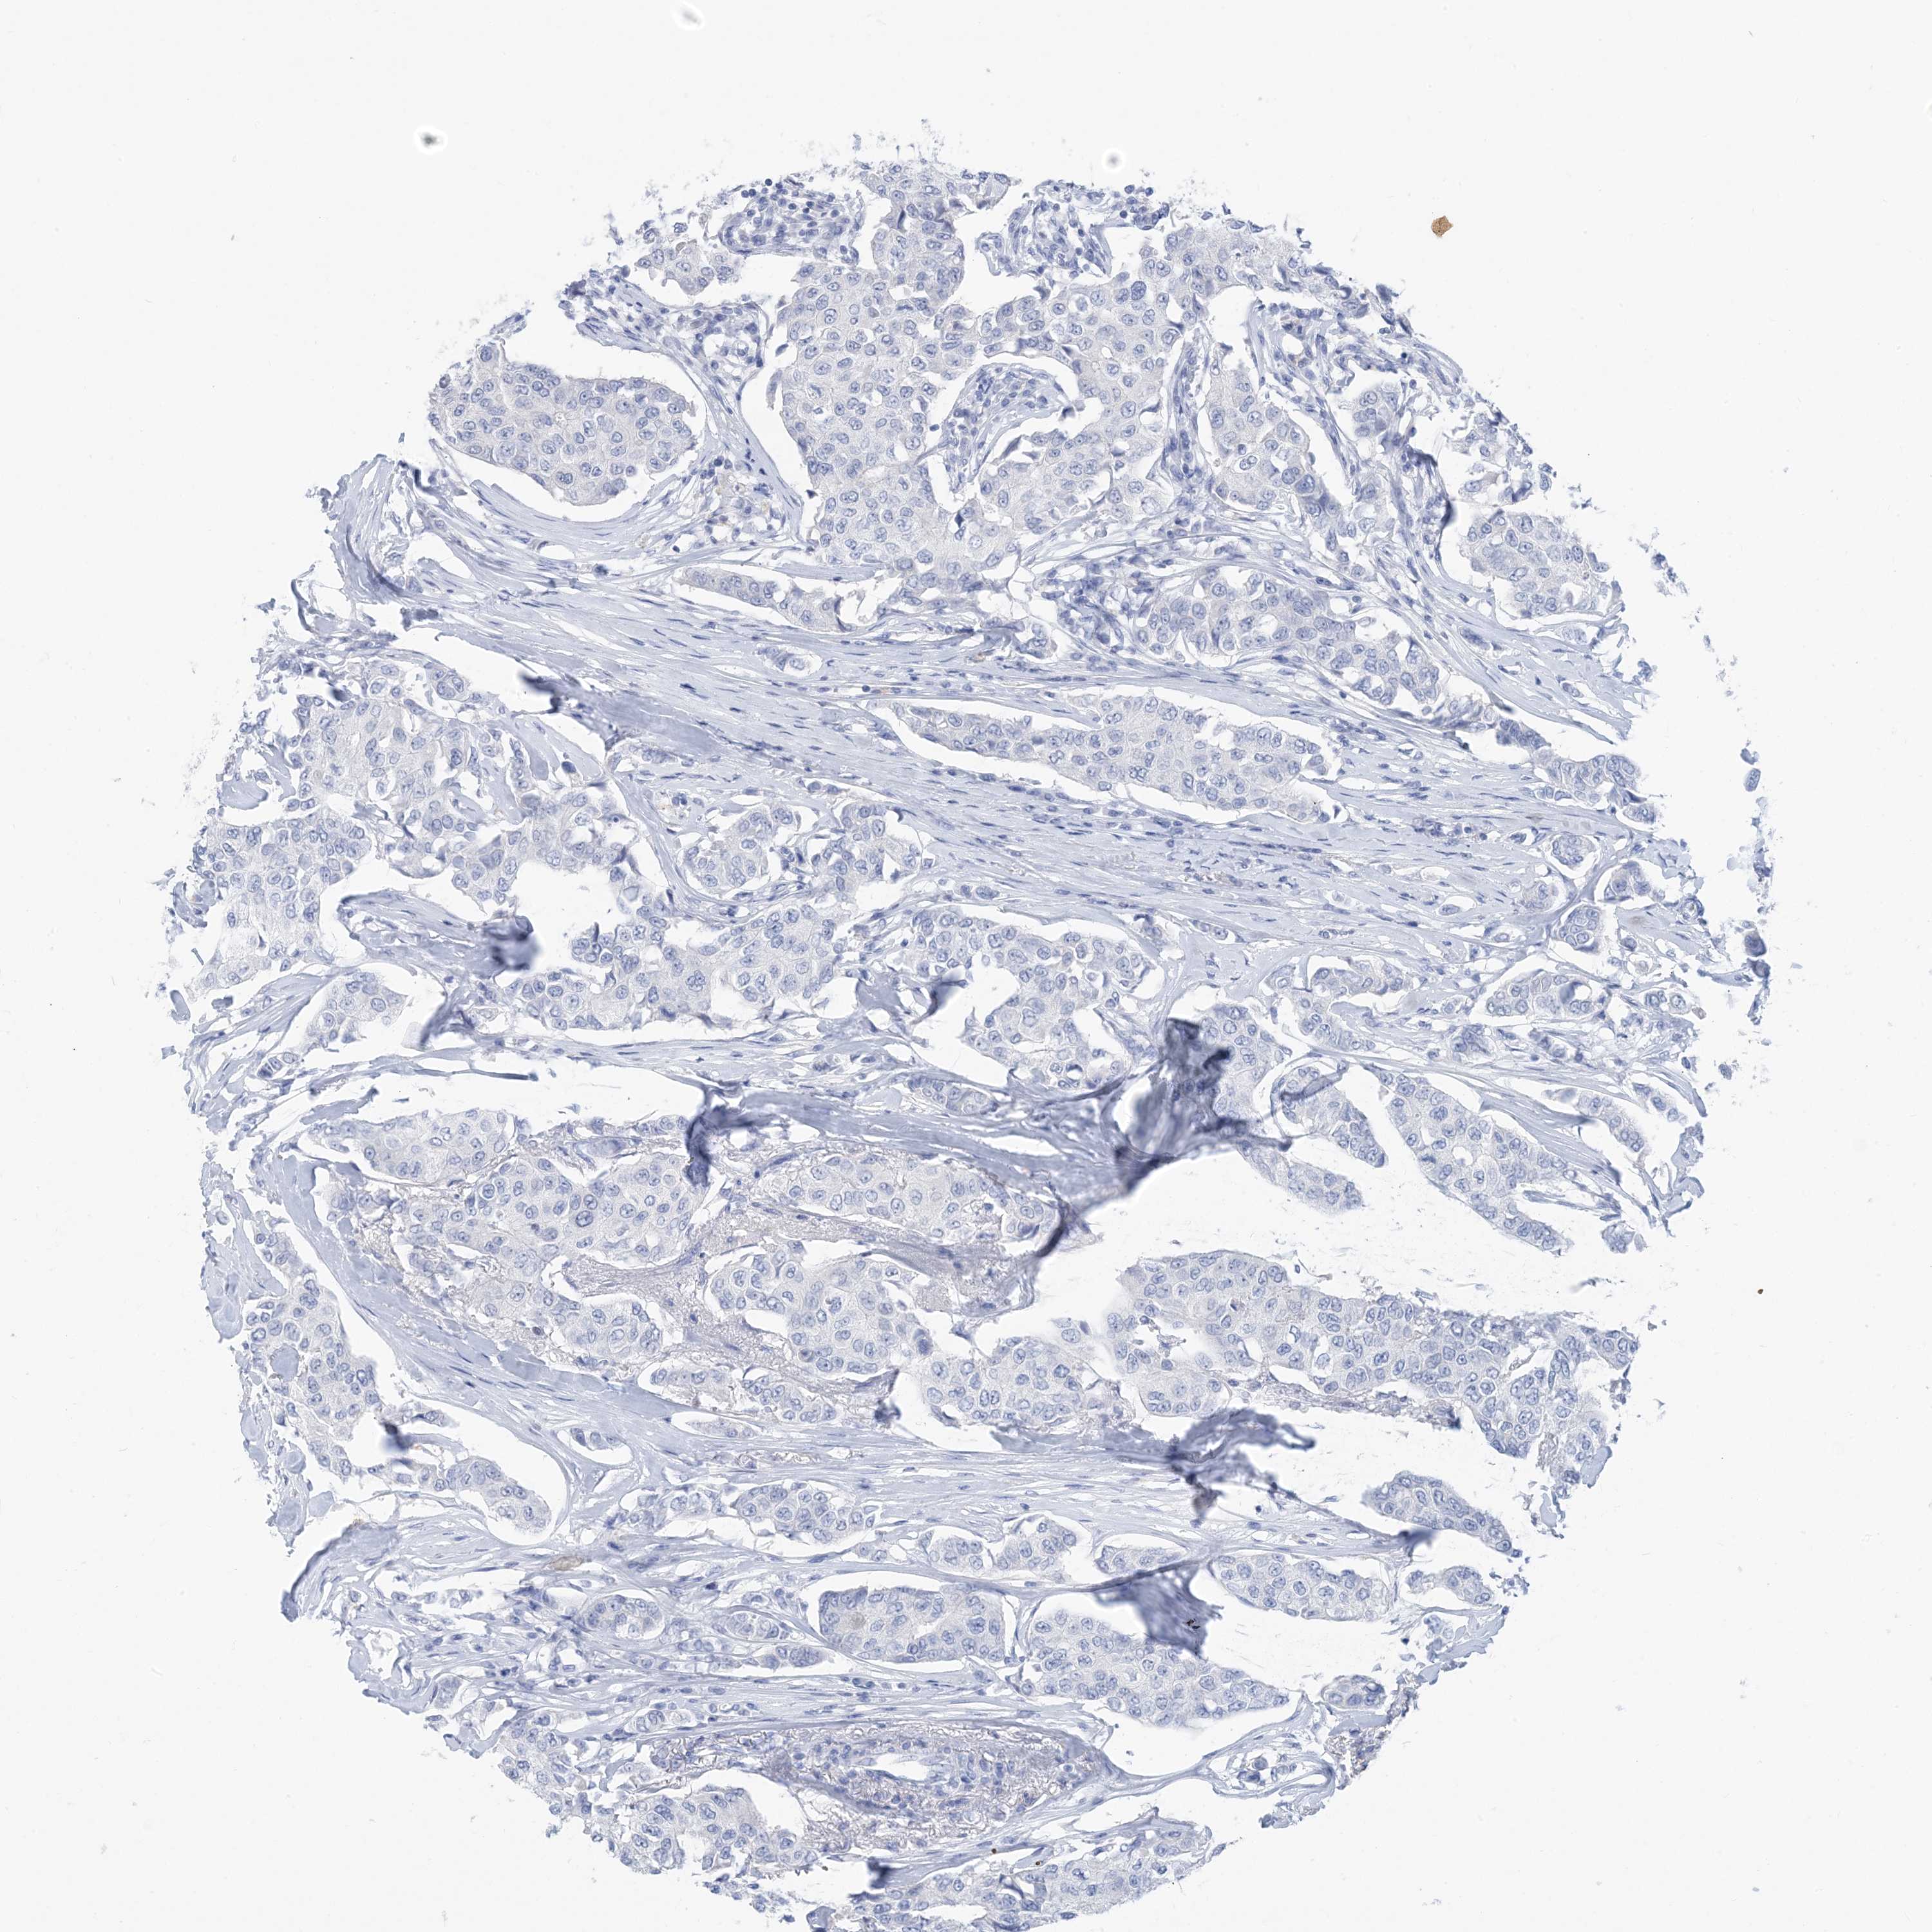

CANCER BREAST CANCER Show tissue menu

Breast cancer

Human cancer

SH3YL1 is not prognostic in Breast Invasive Carcinoma (TCGA)